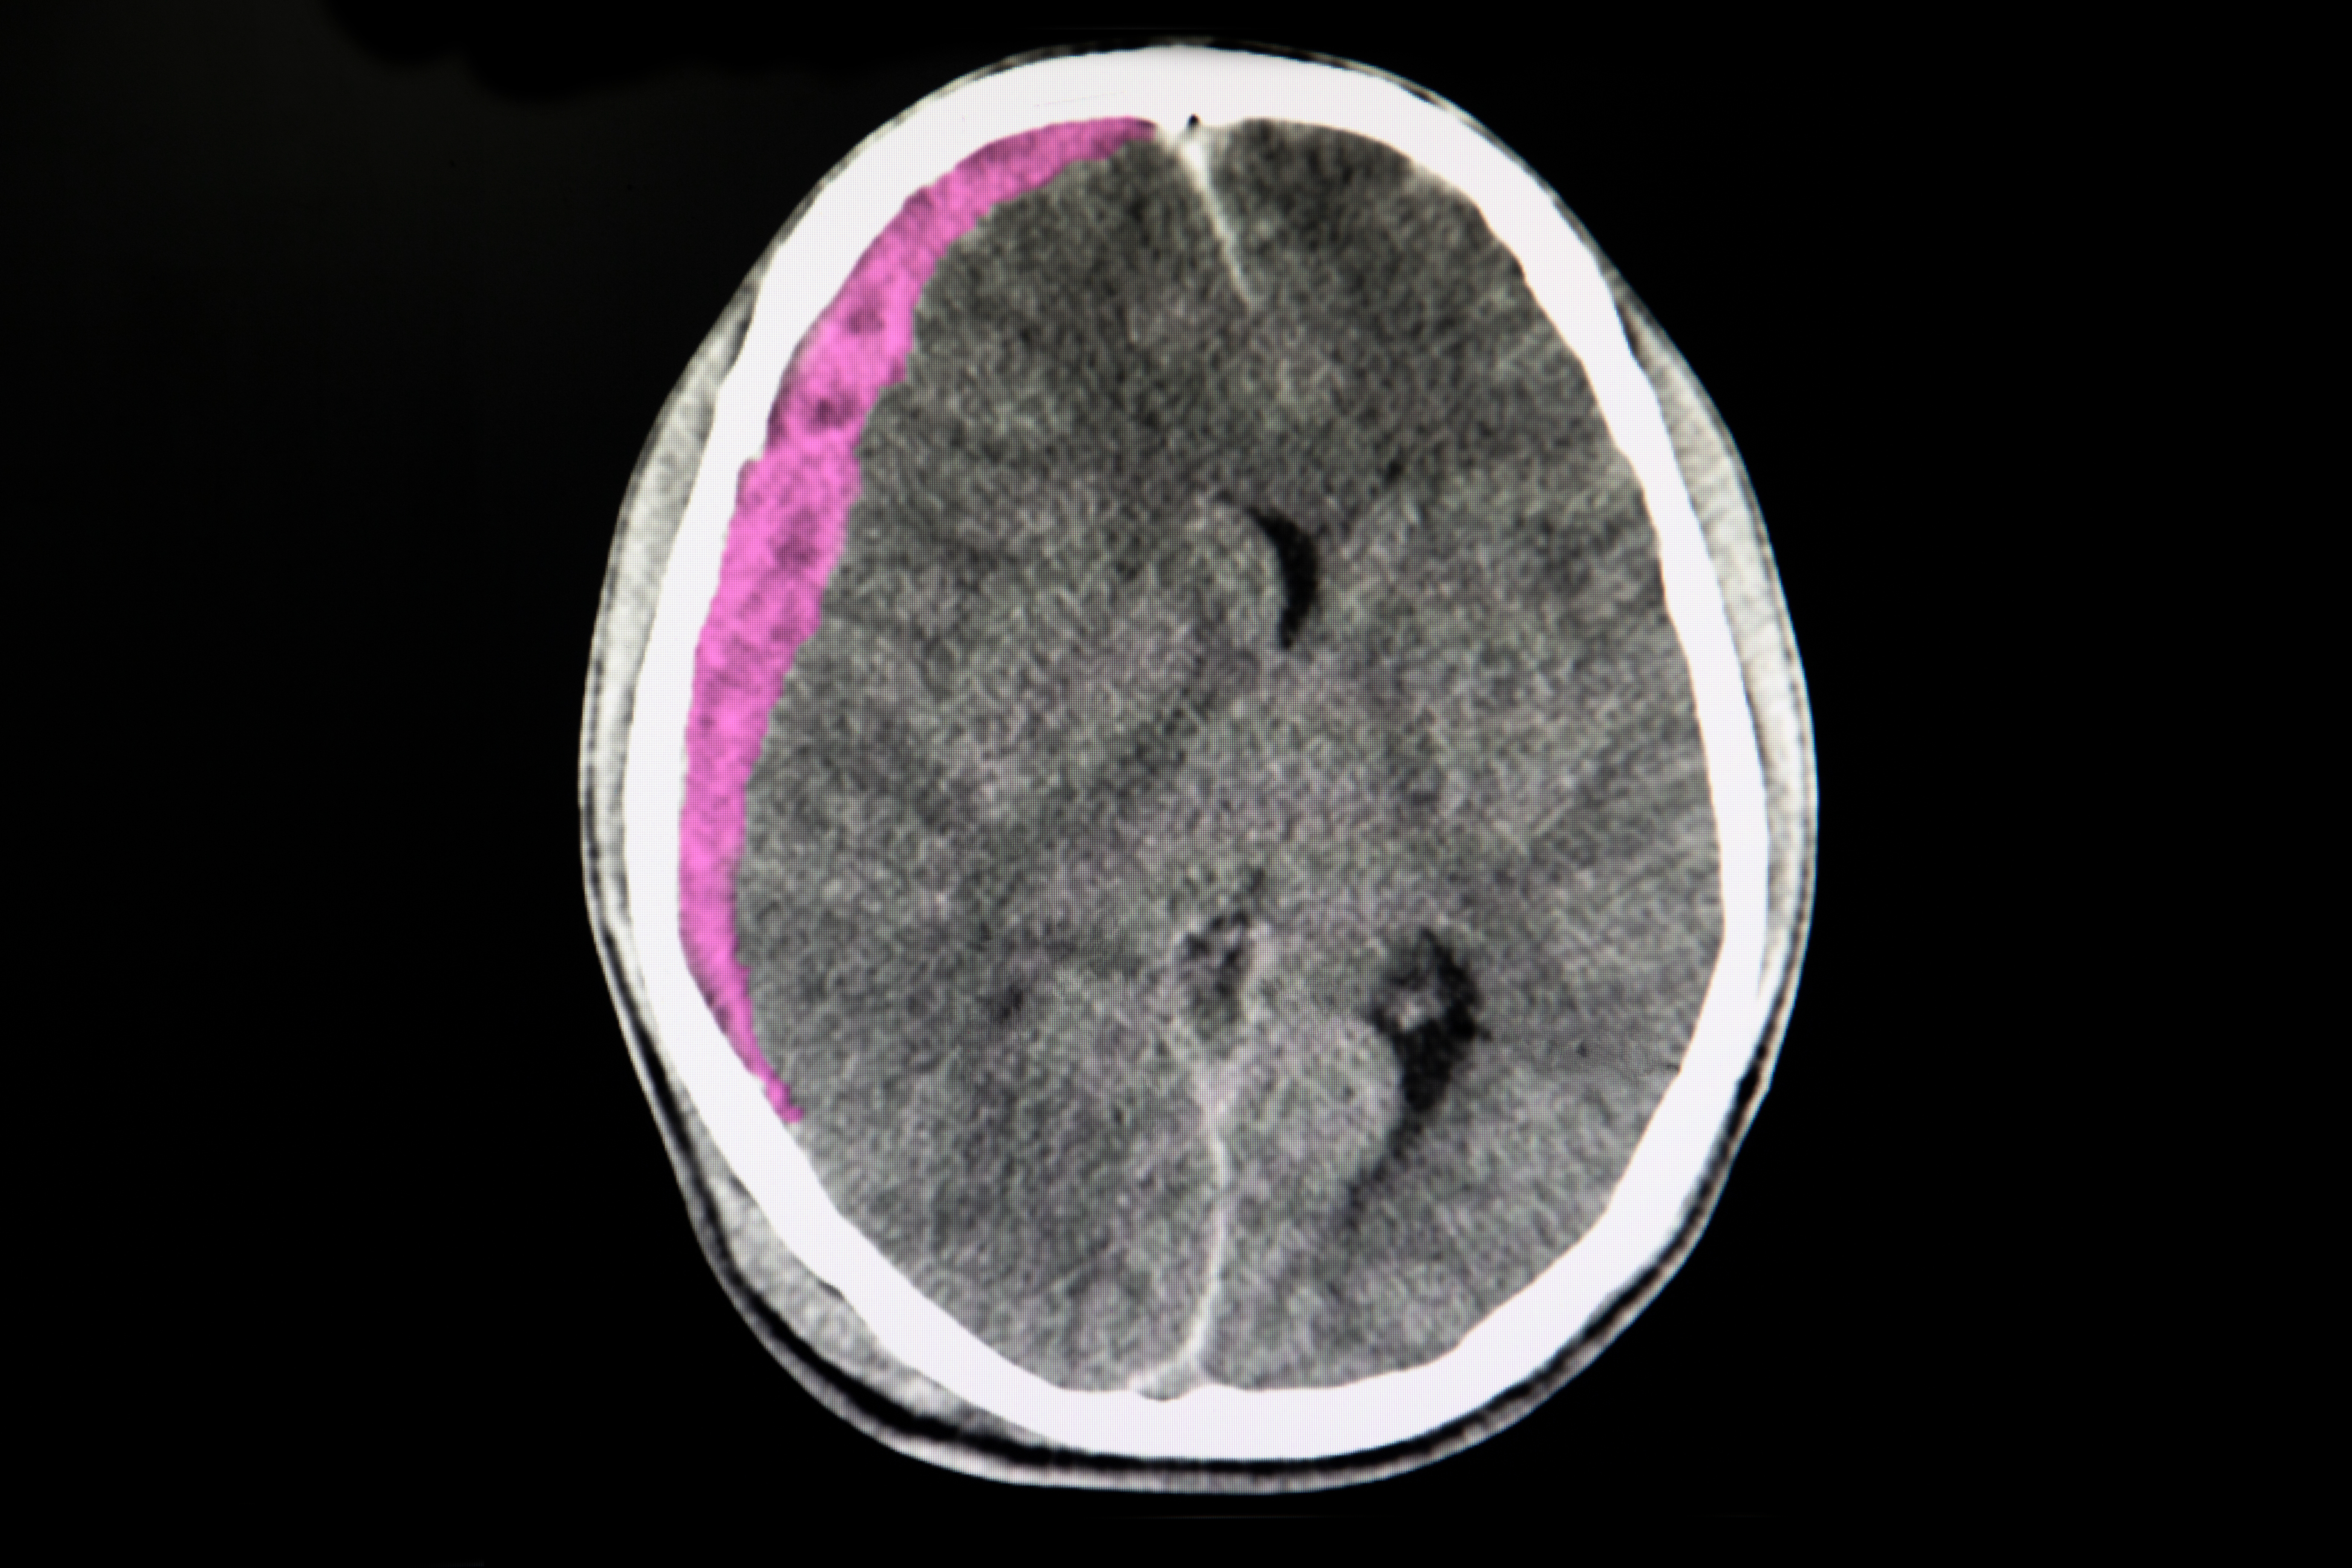

Middle meningeal artery embolization for subdural hematoma

Middle meningeal artery (MMA) embolization can reduce the blood supply to dural vascular membranes, theoretically reducing the rate of subdural hematoma expansion or recurrence. Among 400 patients, those randomized to surgical evacuation plus MMA embolization with Medtronic’s Onyx™ liquid embolic product had a lower rate of hematoma recurrence or progression leading to repeat surgery (4%), compared to 11% for those randomized to surgery alone.

However, embolized patients had nominally higher rates of death at 90 days (5% vs ~3%), functional deterioration (~12% vs ~10%), and disabling stroke (2 patients), leading authors to suggest caution while awaiting further safety data on the procedure. Medtronic funded the trial; the lead author reportedly received $119,033 in direct payments from Medtronic (i.e., that were not associated with any research study) between 2017 and 2023, according to CMS.